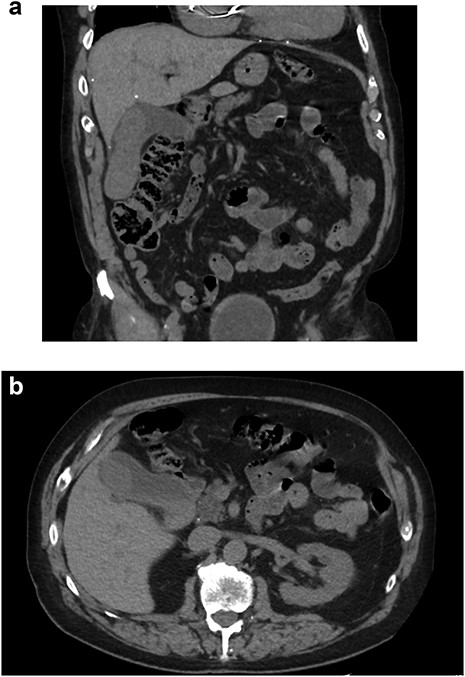

An 81-year-old male presented with the chief complaint of sharp right upper quadrant abdominal pain and nausea ongoing for 12 hours. The patient reported a similar, self-limited, episode 3 months previously. On presentation, leukocytosis 13 × 109/l, aspartate aminotransferase 83 U/l, alanine aminotransferase 49 U/l, lipase 78 U/l (normal 15–65), and total bilirubin 0.7 mg/dl. Abdomen and pelvis computed tomography (CT) demonstrated cholelithiasis in the gallbladder neck, soft tissue attenuation in the fundus of the gallbladder, mild extrahepatic biliary dilation and a common bile duct dilated to 10 mm (Fig. 1). Two well-circumscribed rounded filling defects within the gallbladder lumen, measuring 4.7 × 2.8 × 2.5 cm and 3.4 × 1.4 × 2.2 cm without distal shadowing, were visualized on right upper quadrant ultrasound (Fig. 2). CA 19-9 was negative (6.0 U/l). Magnetic resonance (MR) imaging was unable to be safely performed due to a metal prosthesis.

CT abdomen/pelvis without contrast. (A) Coronal and (B) axial slices depicting cholelithiasis, soft tissue within the gallbladder lumen and extrahepatic biliary ductal dilation